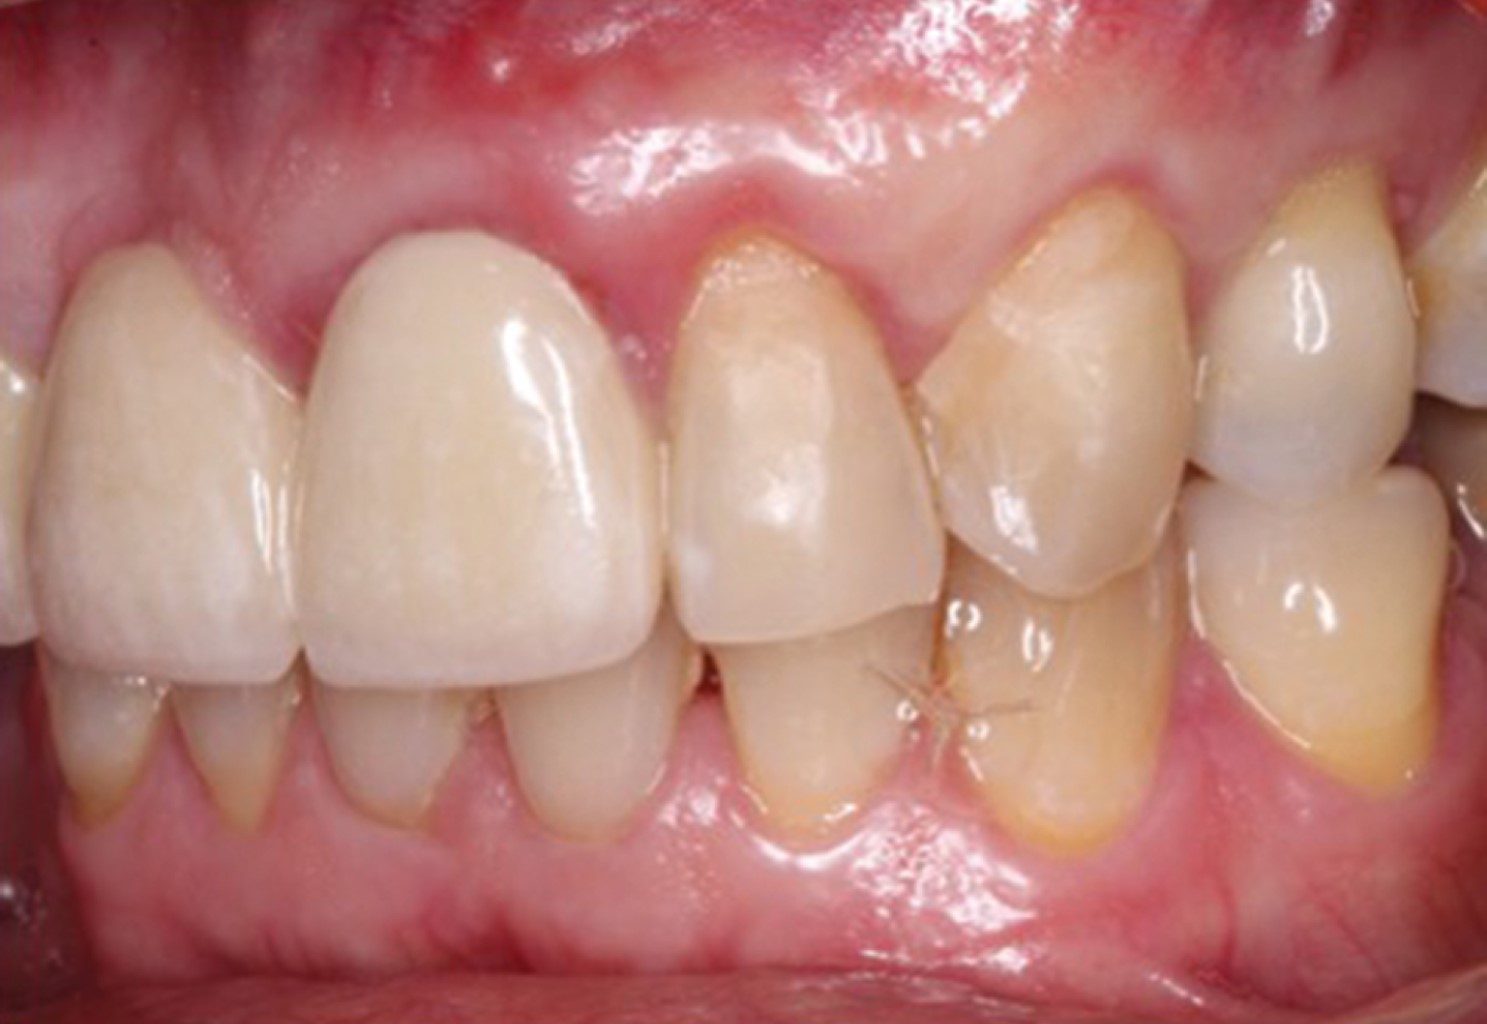

Figure 1